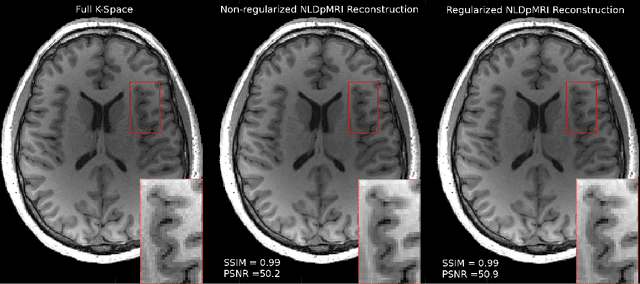

Abstract:Fast data acquisition in Magnetic Resonance Imaging (MRI) is vastly in demand and scan time directly depends on the number of acquired k-space samples. The most common issues in any deep learning-based MRI reconstruction approaches are generalizability and transferability. For different MRI scanner configurations using these approaches, the network must be trained from scratch every time with new training dataset, acquired under new configurations, to be able to provide good reconstruction performance. Here, we propose a new parallel imaging method based on deep neural networks called NLDpMRI to reduce any structured aliasing ambiguities related to the different k-space undersampling patterns for accelerated data acquisition. Two loss functions including non-regularized and regularized are proposed for parallel MRI reconstruction using deep network optimization and we reconstruct MR images by optimizing the proposed loss functions over the network parameters. Unlike any deep learning-based MRI reconstruction approaches, our method doesn't include any training step that the network learns from a large number of training samples and it only needs the single undersampled multi-coil k-space data for reconstruction. Also, the proposed method can handle k-space data with different undersampling patterns, and different number of coils. Unlike most deep learning-based MRI reconstruction methods, our method operates on real-world acquisitions with the complex data format, not on simulated data, real-valued data, or data with added simulated-phase. Experimental results show that the proposed method outperforms the current state-of-the-art GRAPPA reconstruction method.